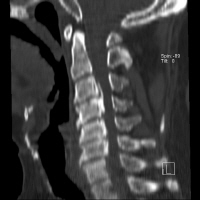

½º¸¶Æ®Æù ¶§¹®¿¡ »ý±â´Â 'ÈÄÁ¾ÀÎ´ë °ñÈÁõ'

[¿Óóµ¥Àϸ®] ¡°ÈÄÁ¾Àδë°ñÈÁõ°ú ¸ñµð½ºÅ©°¡ °°ÀÌ Àִµ¥¿ä ¤Ð ...

¡°½º¸¶Æ®Æù ¶§¹®¿¡ »ý±â´Â ¸ñÁúȯ, ÈÄÁ¾ÀÎ´ë °ñÈÁõ ÁÖÀÇÇØ¾ß¡±

[¿Óóµ¥Àϸ®] ½º¸¶Æ®ÆùÀÇ »ç¿ëÀÌ ´Ã¾î³ª¸é¼ ¸ñµð½ºÅ© µîÀÇ ¸ñ ...

ÂòÁú¹æ ³ôÀº ¸ñ º£°³, ¸ñ µð½ºÅ© Á¶½ÉÇϼ¼¿ä

[¿Óóµ¥Àϸ®] ȯÀý±â·Î ÀÎÇØ ½±°Ô ÇǷΰ¡ ½×À̱⵵ ÇÏ°í ¸öµµ ¿©...